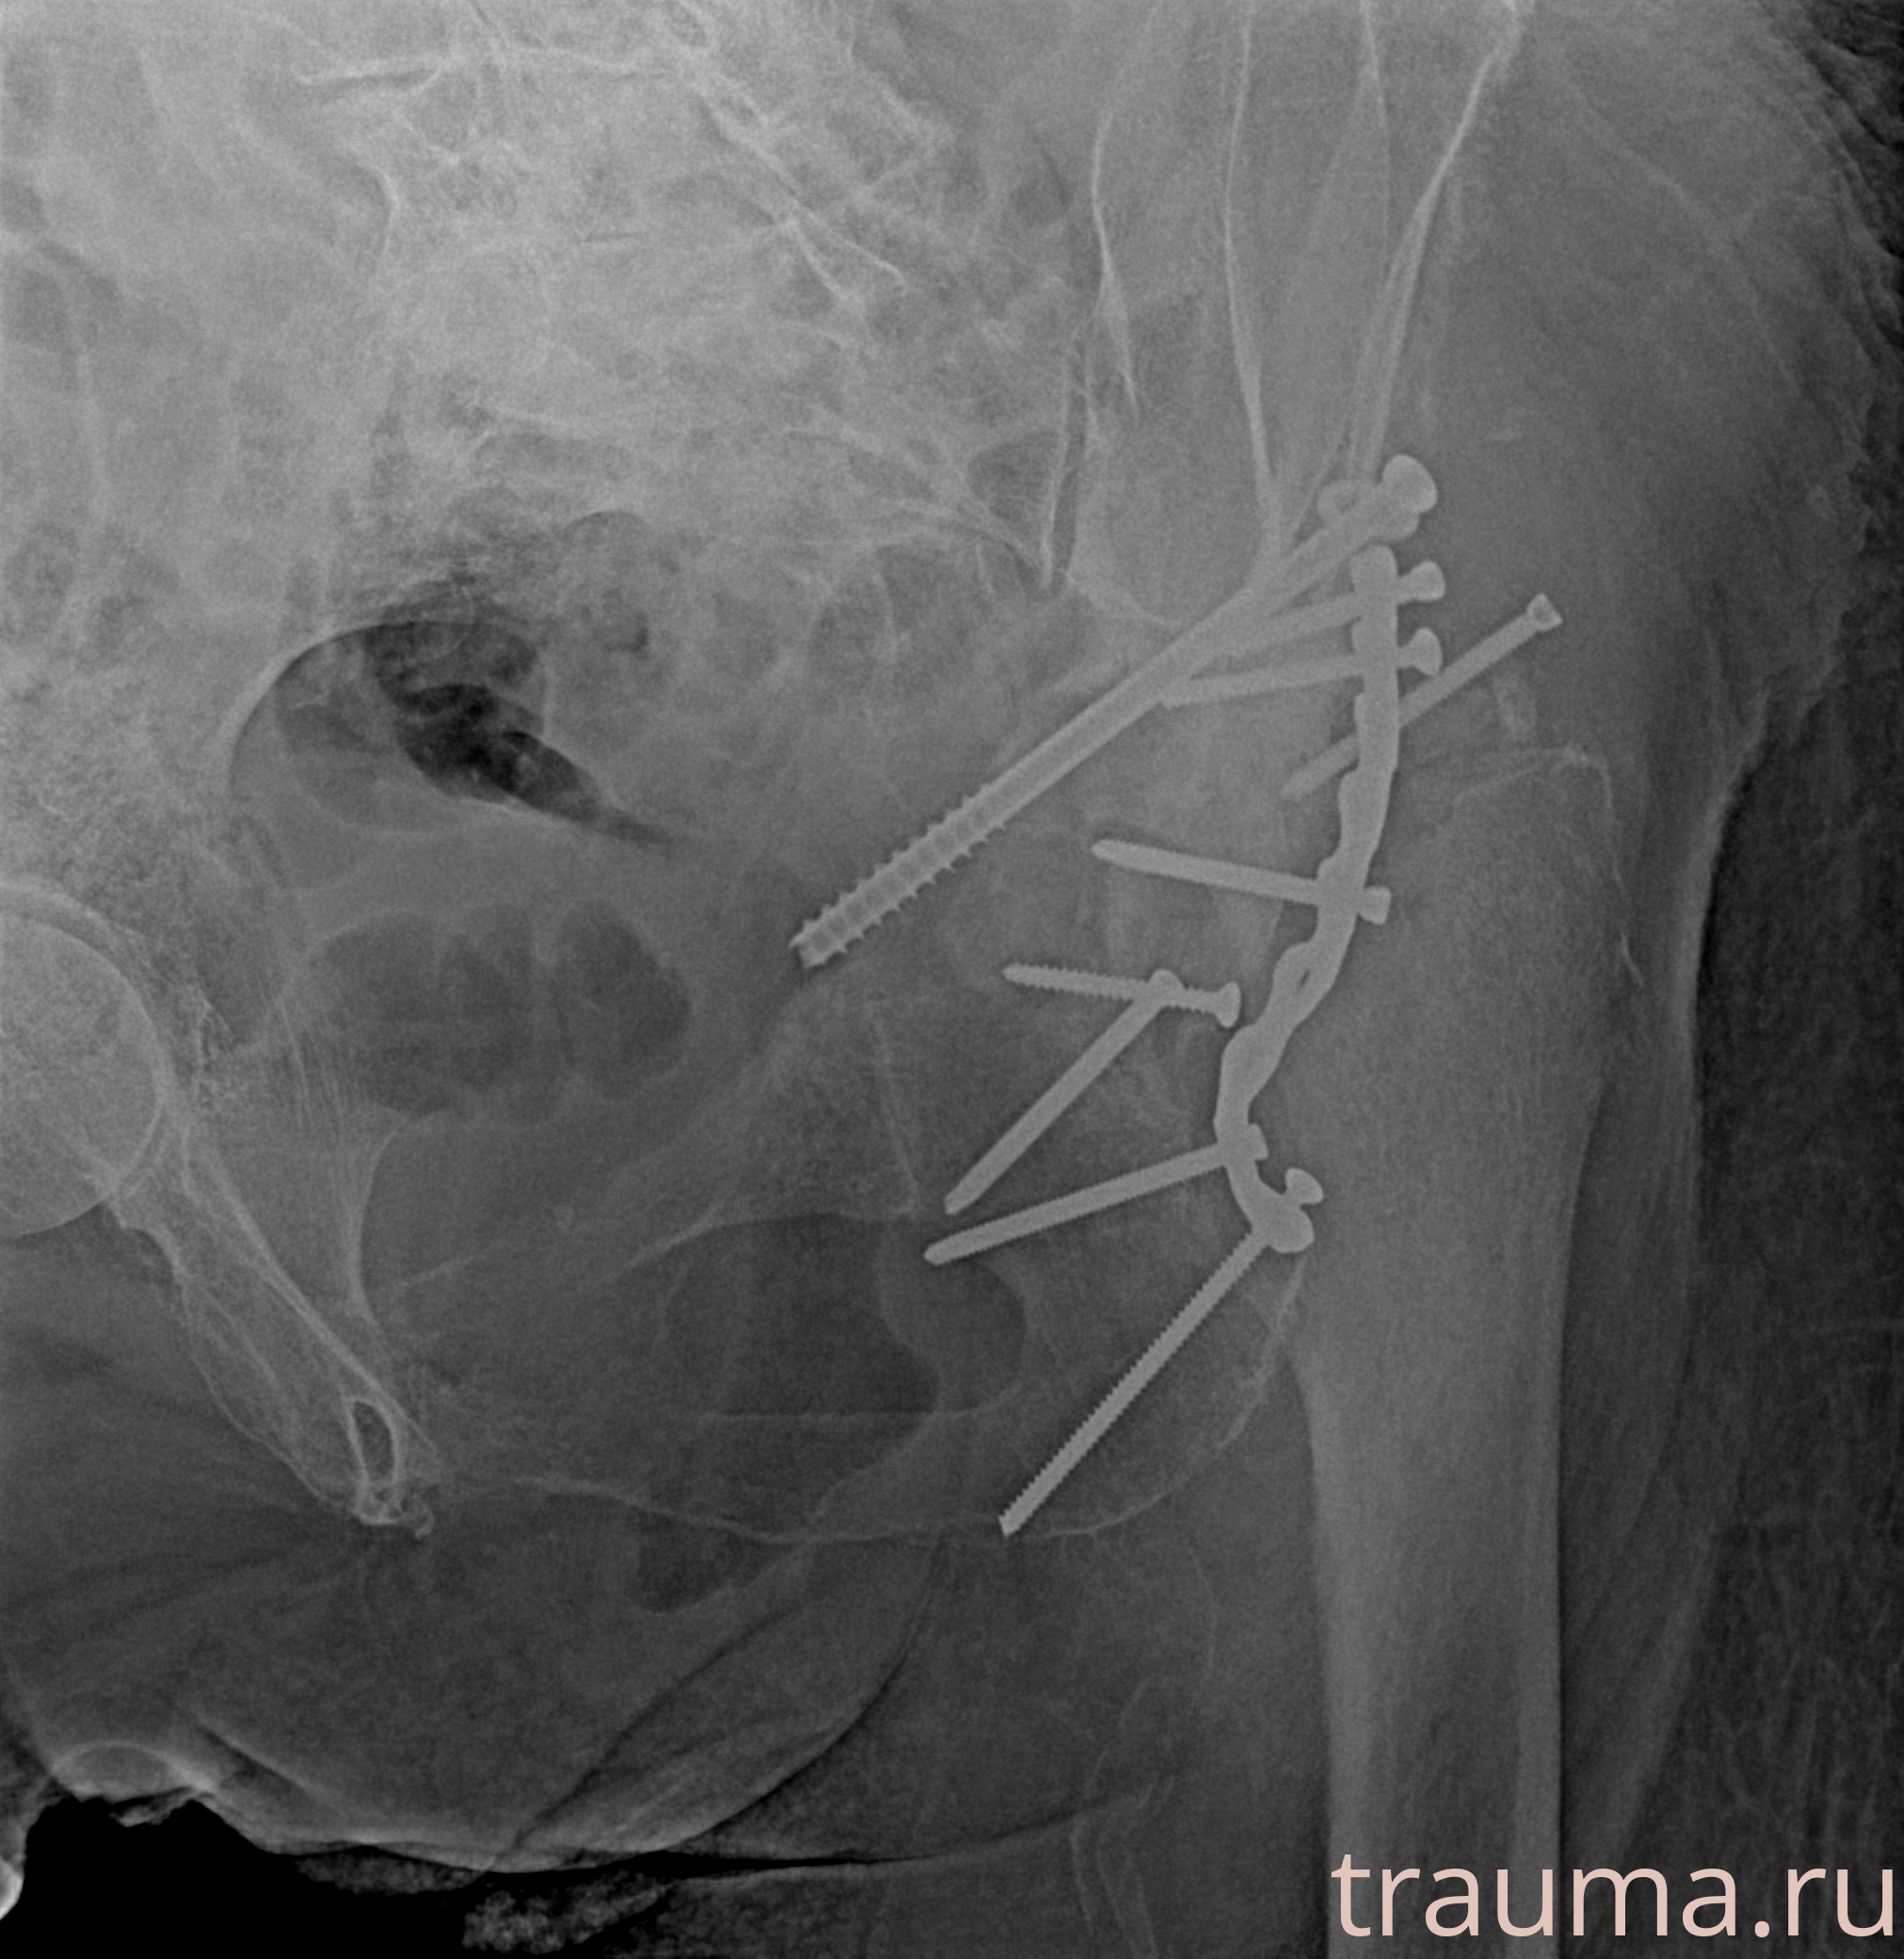

Рентгенограммы

Рентген на дому: по вашему адресу приезжает врач-рентгенолог, травматолог-ортопед с мобильным рентгеновским аппаратом, проводит диагностику травмы или заболевания, делает необходимые рентгенограммы, дает рекомендации по дальнейшему лечению. Получить качественные снимки в домашних условиях возможно благодаря уникальной методике, разработанной МосРентген Центром для института  Склифосовского